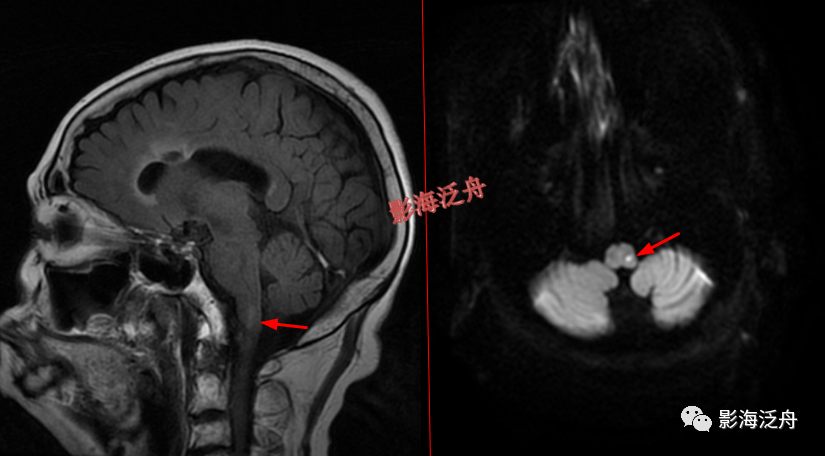

右侧CPA区听神经瘤

(红箭)。有些单位使用1.5T MR,对蝶鞍区及幕下结构的显示会不太理想,再加上本例患者的桥小脑角池发育的比较狭窄,不能把病灶很好的衬托出来,此时就很容易造成漏诊。

椎基底动脉迂曲走行导致邻近延髓受压,也是比较常见的,虽然算不上漏诊,但笔者认为这种病理性改变还是应当在报告中体现出来。